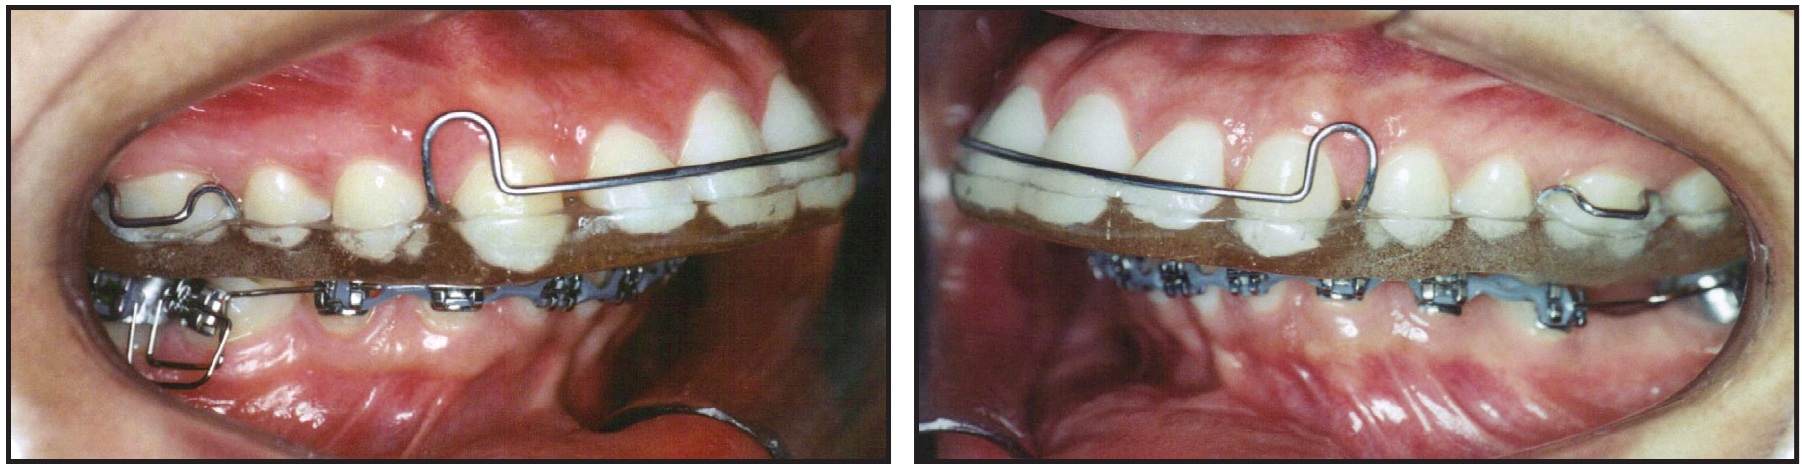

A maxillary alginate impression was obtained for fabrication of a removable full-coverage maxillary splint to open the bite and allow bonding of the mandibular fixed appliances (Fig. 2).

Fig. 2 Full-coverage maxillary splint and initial mandibular standard edgewise appliances.

The splint was adjusted with the patient in centric relation, following Dawson's bilateral manipulation technique to ensure simultaneous bilateral contacts of similar intensity in centric occlusion.7

Mandibular .022" x .028" standard edgewise appliances* were bonded from second molar to second molar for leveling and alignment, with archwires progressing up to .020" stainless steel*. The maxillary splint was adjusted at each monthly appointment to eliminate potential interferences created by the changes in tooth positions. Six months into treatment, the patient was able to occlude without contacting the lower brackets, and the splint was discontinued.